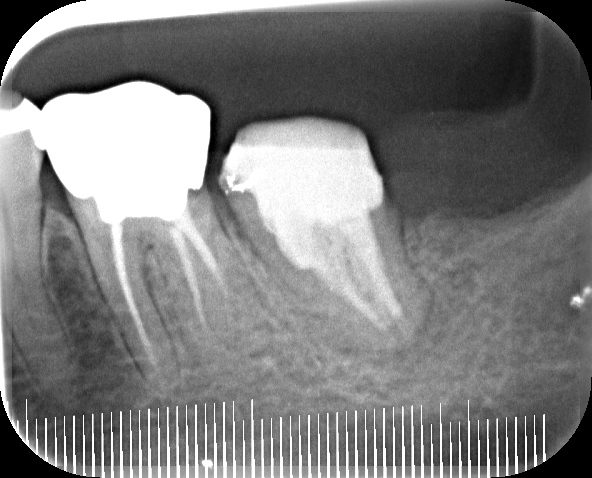

左下他院で抜歯と言われて、セカンドオピニオンで来院されました

after

| ① 患者様の主訴 | 左下腫れている |

| ② 診断結果 | 慢性化膿性根尖性歯周炎 |

| ③ 治療内容 | マイクロスコープ、ラバーダムを使用した精密根管治療 |

| ④ 治療後経過 | 術後5年、経過良好 |

| ⑤ 治療期間 | 1ヶ月 |

| ⑥ 治療費用 | 165,000円 |

| ⑦ リスク・副作用 | 歯根破折や病変再燃の場合は抜歯または外科的歯内療法 |